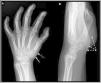

Synovial sarcoma (SS) is a rare malignant neoplasm of the soft tissue adjacent to joints. It is the most commonly diagnosed non-rhabdomyosarcoma soft-tissue sarcoma (STS) in childhood (30%). Its most frequent location is the knee and ankle, and it is the most common STS to affect the foot. Unlike other STS, it has slow growth and an earlier age at diagnosis (adolescents and young adults), which is why many cases are initially misdiagnosed as benign processes. Magnetic resonance imaging (MRI) is key due to its characterisation capabilities as SS shares features with other STS. Definitive diagnosis is achieved through a pathological study that shows the pathognomonic translocation t(x;18)(p11;q11) with the fluorescence in situ hybridisation (FISH) technique. The objective of this article is to highlight the key characteristics that are useful for diagnosing SS, fundamentally through the use of radiological imaging techniques, as well as nuclear medicine and pathological studies, illustrated with cases diagnosed in our centre.

El sarcoma sinovial (SS) es una neoplasia maligna infrecuente del tejido blando adyacente a las articulaciones, siendo el sarcoma de tejidos blandos (STB) de tipo «no rabdomiosarcoma», más diagnosticado en la infancia (30%). Su localización más frecuente es la rodilla y tobillo, representando el STB más común del pie. A diferencia de otros STB, presenta un crecimiento lento y una edad más temprana al diagnóstico (adolescentes y adultos jóvenes), por lo que muchos casos son inicialmente diagnosticados como procesos benignos de forma errónea. La resonancia magnética (RM) es clave para su caracterización, si bien comparte características con otros STB. El diagnóstico definitivo es anatomopatológico, que evidencia la translocación patognomónica t(x;18)(p11;q11) con técnica de hibridación fluorescente in situ (FISH). El objetivo de este artículo, ilustrado con casos diagnosticados en nuestro centro, es resaltar las características claves para el enfoque diagnóstico del SS, fundamentalmente mediante el uso de técnicas de imagen radiológicas, así como estudios de medicina nuclear y anatomopatológicos.